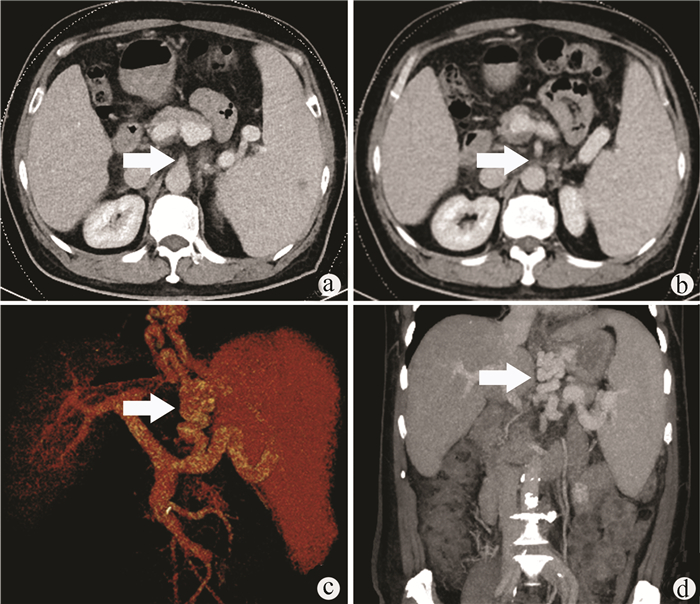

Follicular dendritic cell sarcoma of the liver: A case report

Chenguang LI, Jiyao JIA, Luanbiao SUN, Shuohui GAO

2022, 38(1): 174-176. DOI: 10.3969/j.issn.1001-5256.2022.01.029

Abstract(1641) HTML (462) PDF (2854KB)(73)

Abstract: